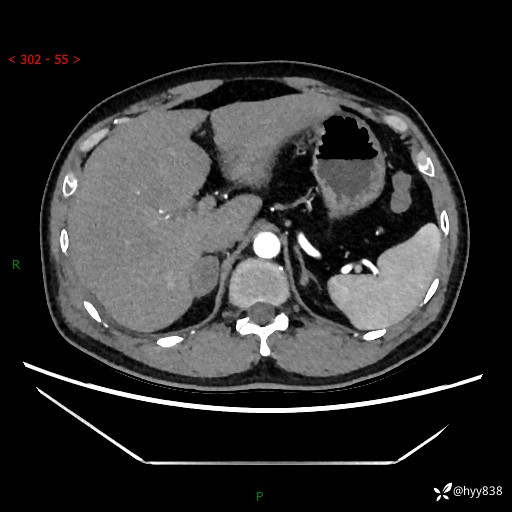

现病史:患者9月4日摔伤在深圳市宝安区中心医院行CT检查提示右侧肾上腺区结节(38*27mm),复查B超提示右侧肾上腺区可见一61*24mm异常低回声团,建议进一步检查。进一步完善增强CT后提示:右侧肾上腺区肿块及周围渗出改变,大致同前,考虑肾上腺腺瘤,不除外瘤内出血可能,否认阵发性头晕、头痛、出汗、乏力等不适,门诊以“ 右侧肾上腺肿瘤”收入住院。 起病来,患者精神、食欲、睡眠可,大便通畅,小便如上述,体力体重无明显改变。

肾上腺CT平扫

增强(动脉期+静脉期)